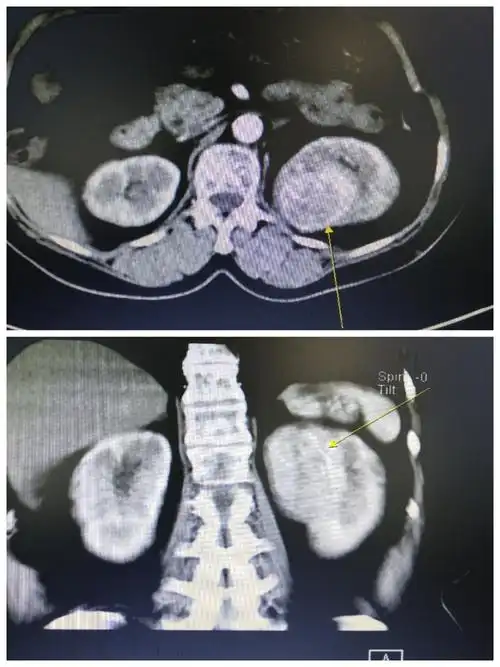

病例赏析 | 腰痛伴血尿,少见且典型的肾肿瘤请你来看

患者,女,70岁,住院常规检查发现左肾占位.在我科行泌尿系ct增强扫描!